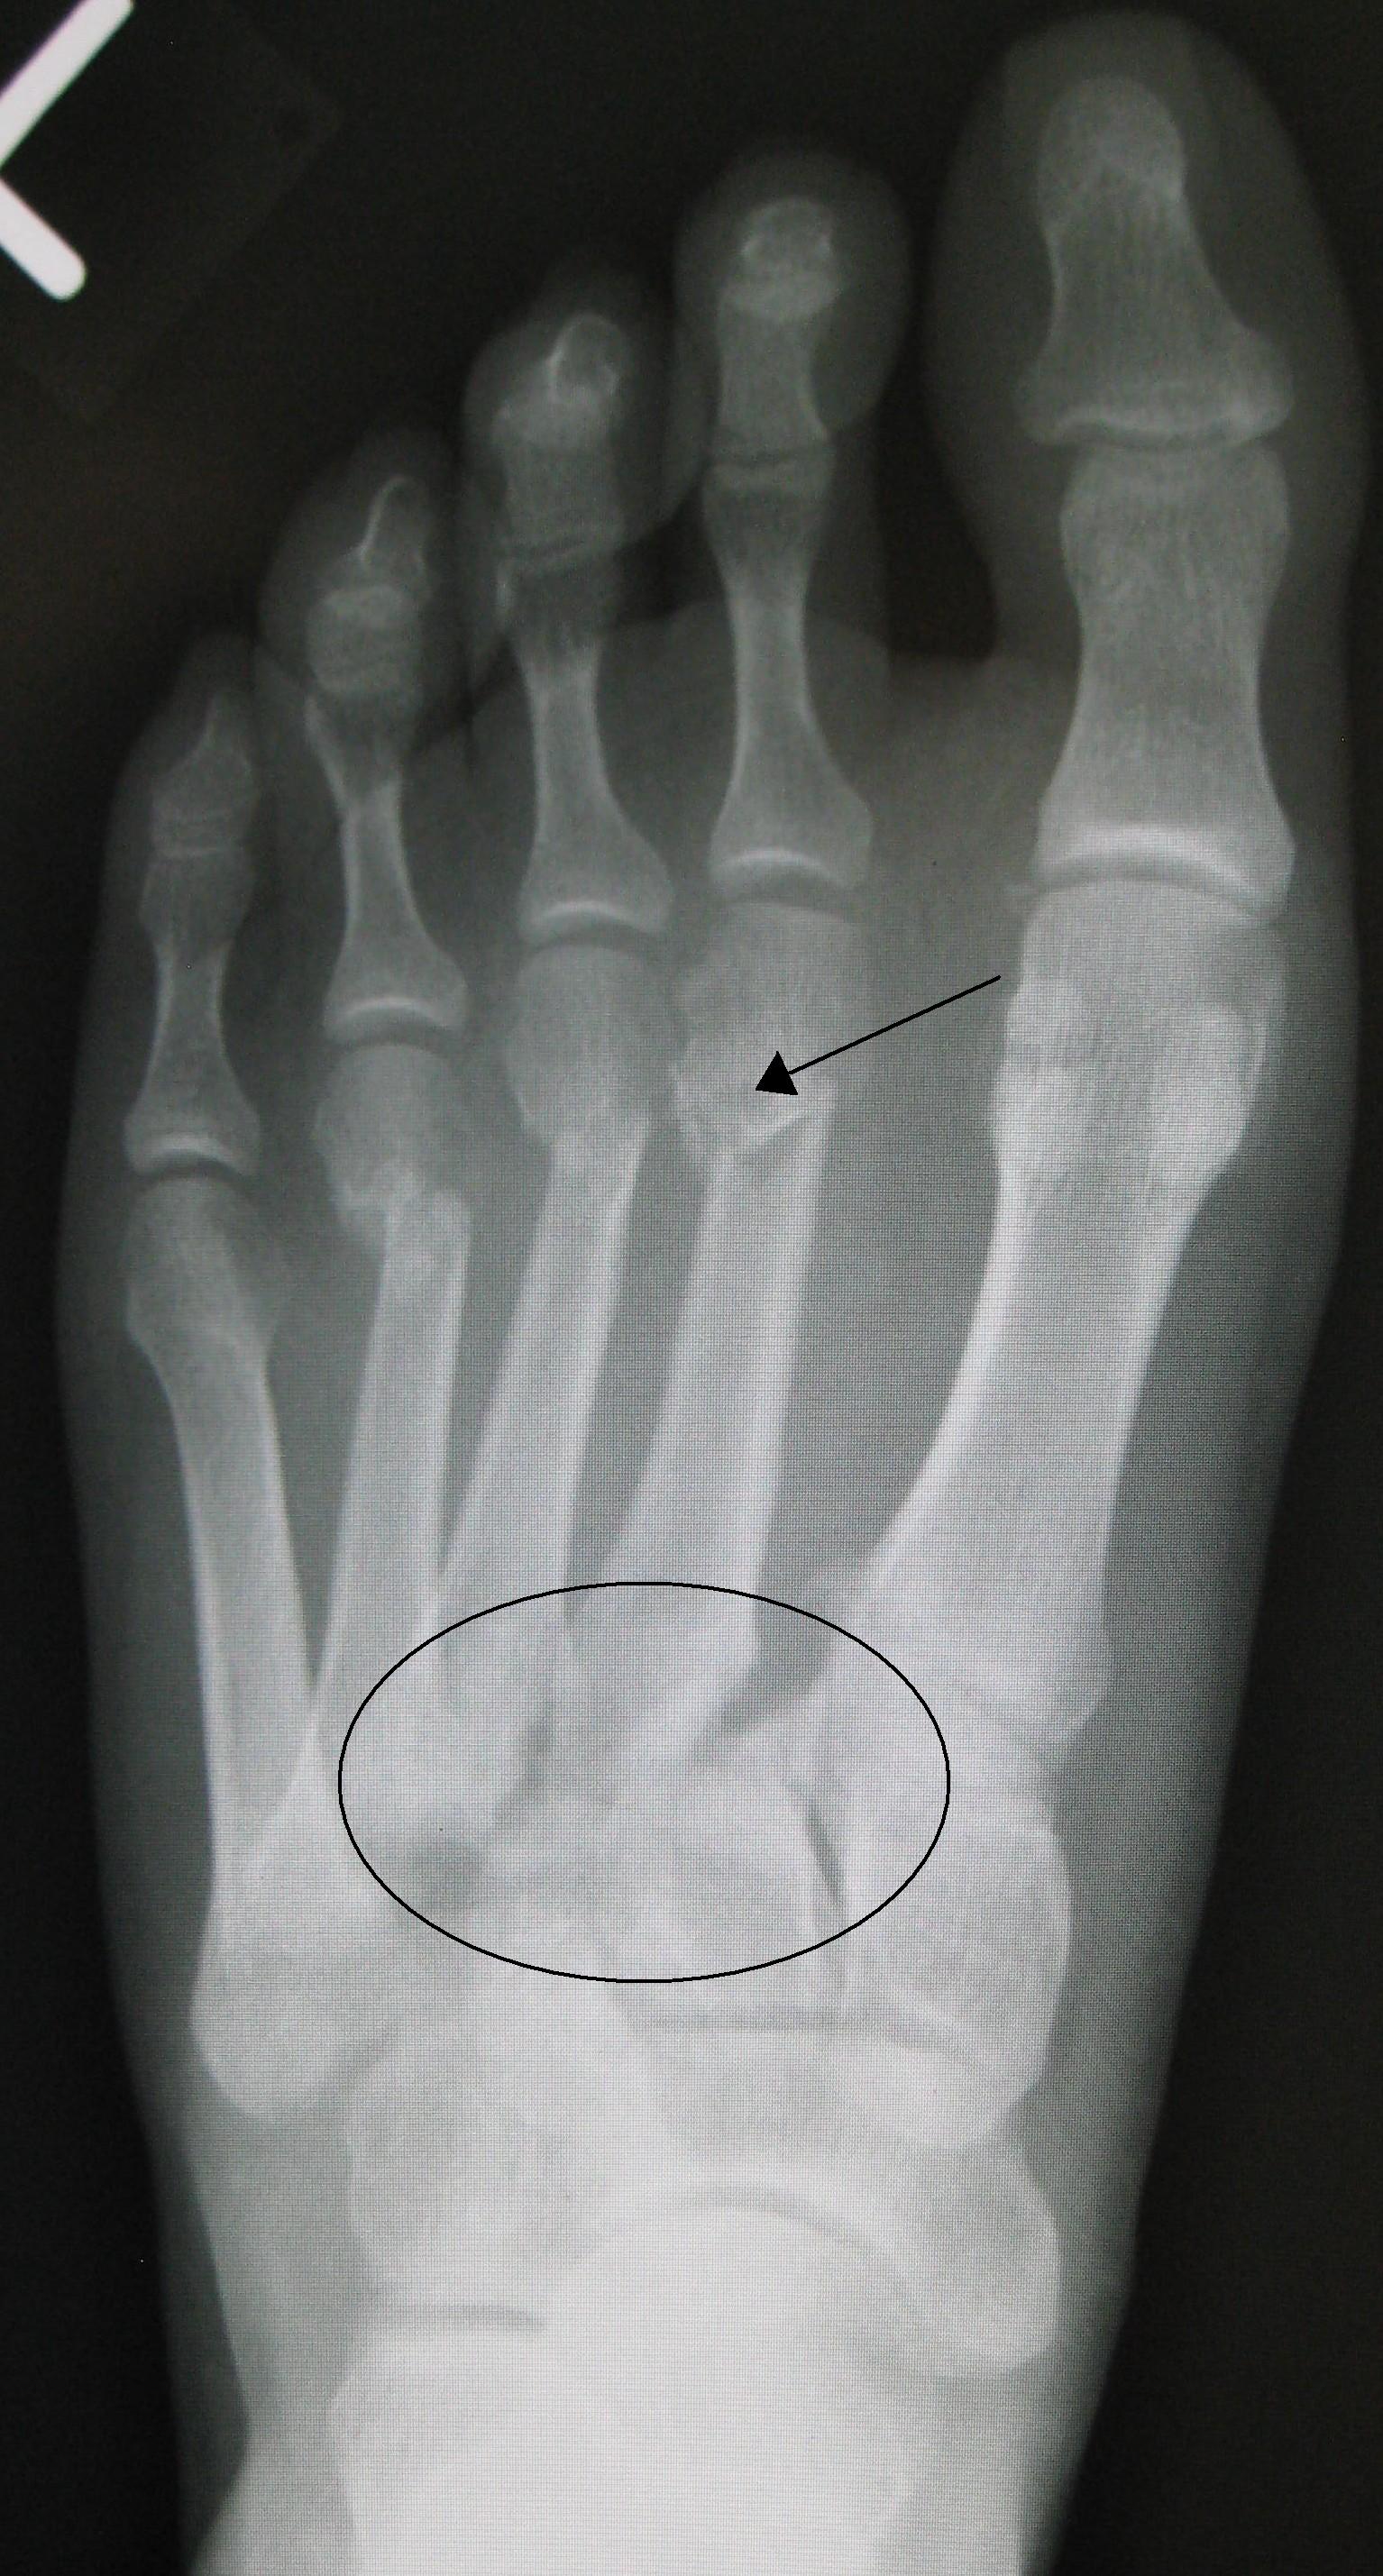

The anatomy of the human foot is labeled into three distinct parts, the hind (rear), mid and forefoot. The Lizfranc joint or complex is comprised of the medial aspect of the mid-foot or mid-tarsal joint. The joint is made up of the 1st and 2nd metatarsal and 1st and 2nd cuneiform bones. The proximal end of the 2nd metatarsal or base “wedges” itself into the “keystone” or 2nd cuneiform bone. This bony alignment leads to a very stable juncture that is capable of transferring the forces from the rear or hind foot to the forefoot during gait. The joint is held together on the bottom or plantar surface with a thick ligament (leather-like in nature) that is capable of withstanding hundreds of pounds of force without being disrupted. The superior aspect of the joint is not well stabilized and is the “weak” part of the joint. When an injury occurs, there are varying degrees of damage to the structures of the joint.

Diagnosing these injuries is difficult. A normal x-ray does not usually reveal any damage to the joint because it is taken in a non-weight bearing position. If the x-ray is performed in the weight bearing position it often times reveals a larger gap or space between the cuneiforms and this is an indication that the joint has sustained some damage and laxity most likely is present. More advanced testing, MRI and CT scans are not required to diagnose a Lizfranc injury, but some doctors rely on these tests if there are question about the diagnosis or if surgery is required to fix the damaged joint.